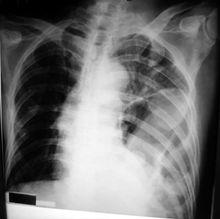

檢查骨折

胸片右圖示右側多發肋骨骨折及氣胸可見多出肋骨的骨質連續性中斷。

右肺不見肺紋理。

檢查氣胸

見上圖,右肺無肺紋理,

右肺被氣胸擠壓